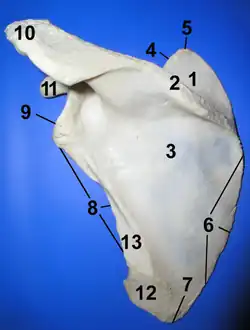

Left scapula. Posterior view. Acromion is "10"

Left scapula. Posterior view. Acromion is "10" -